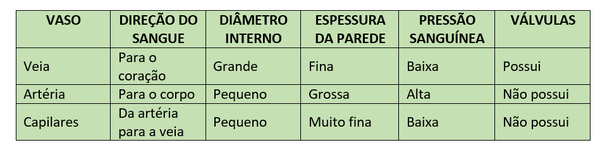

As veias, quando comparadas com artérias do mesmo calibre, possuem uma parede mais fina e um diâmetro maior e irregular. Além disso, elas apresentam válvulas que impedem o refluxo do sangue.

As veias são caracterizadas por:

- Transporte de sangue venoso do corpo para o coração – a veia pulmonária é a exceção, pois ela transporta sangue oxigenado dos pulmões de volta ao coração;

- Cavidade interna grande, o que reduz a fricção quando o sangue é transportado;

- Sangue sendo movido em baixa pressão;

- Não possuir muitos músculos e fibras elásticas associadas a elas;

- Presença de válvulas para prevenir que o sangue sofra refluxo quando transportado contra a gravidade.

É comum, no entanto, as pessoas confundirem os vasos sanguíneos. Confira, abaixo, as características de cada um: